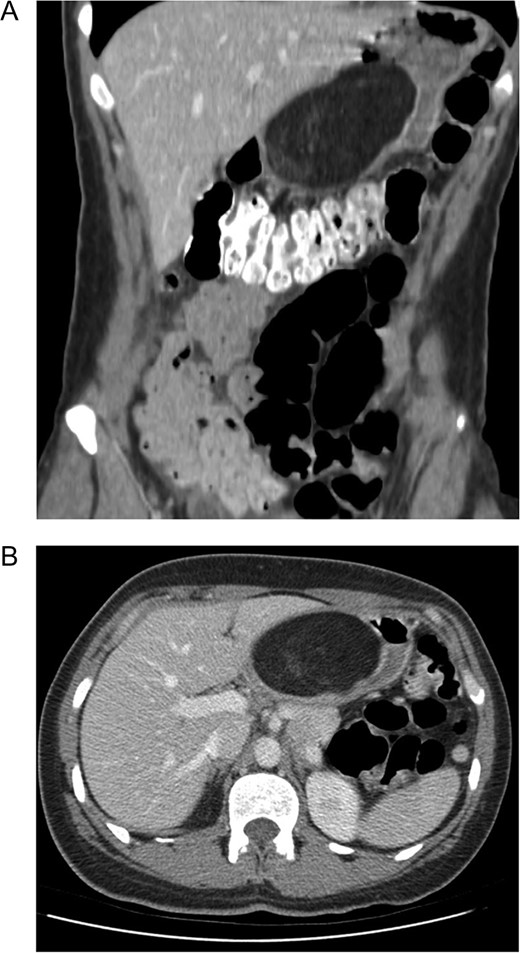

A 39-year-old female presented to her primary care physician with ~1 year of upper GI bleeding. She was a recent Ukrainian immigrant and had not undergone previous evaluation. She was referred to a gastroenterologist and underwent upper endoscopy with mucosal biopsy of a large antral mass. She declined endoscopic ultrasound (EUS) and was briefly lost to follow up over the course of a pregnancy. She returned to seek care for ongoing anemia and new epigastric pain. Esophagogastroduodenoscopy (EGD) with EUS was performed identifying a 6 cm mass within the muscularis propria of the antrum. Based on these findings, she was referred to a surgeon and underwent pre-operative computed tomography (CT) of the abdomen and pelvis which demonstrated a 9.7 Ă— 7.8 Ă— 4.8 cm3, heterogeneous mass with internal septa adherent to the posterior wall of the gastric antrum (Figs 1 and 2).

Computer tomography demonstrating a large (9.7 Ă— 7.8 Ă— 4.8 cm3) mural based mass extending along the posterior wall of the lesser curve of the stomach, effacing the lumen. (A) Coronal. (B) Axial. The mass contains predominantly fat signal with areas of hazy internal enhancement. No pathological lymphadenopathy was noted.